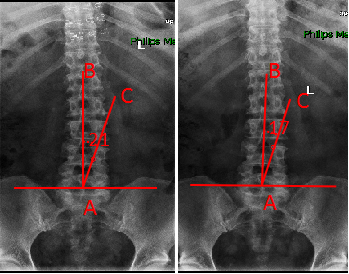

治疗前后脊柱侧凸角度对比

治疗前 治疗后